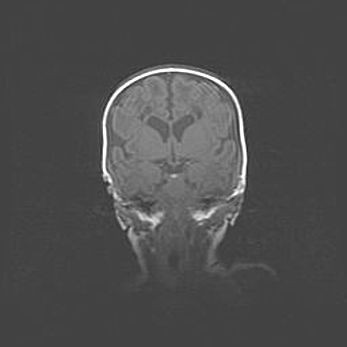

Сообщающаяся гидроцефалия. Кистозная энцефаломаляция головного мозга.

Возраст: 3 месяца 4 дня

Вес: 3100 г

Пол: женский

Окружность головы: 34 см

Срок гестации: 31 неделя

Кистозная энцефаломаляция головного мозга - одна из форм поражения головного мозга в детском возрасте. Характеризуется возникновением множественных и распространённых кист в коре, белом веществе и подкорковых образованиях головного мозга у плодов, новорождённых и детей раннего возраста. Развитие кистозной энцефаломаляции связано с внутриутробной асфиксией и гипотонией, родовой травмой, тромбозом синусов, пороками развития сосудов, инфекциями, сепсисом и другими причинами. Наиболее значимые инфекционные агенты: вирусы простого герпеса, цитомегалии, краснухи, токсоплазмы, энтеробактерии, золотистый стафилококк и другие.